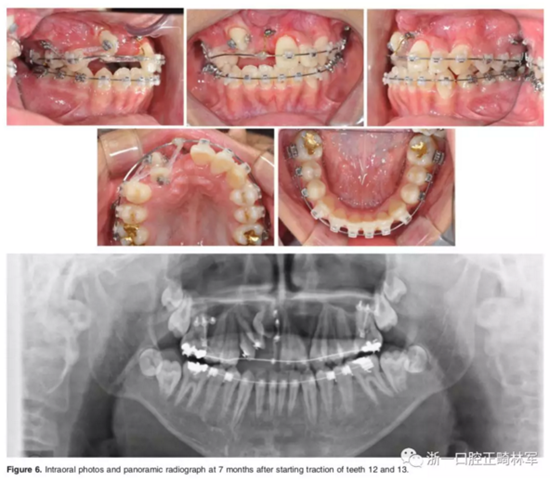

弓絲換至0.019*0.025-inch不銹鋼絲時,開始進行外科手術暴露阻生牙。由于易位情況嚴重,三維向阻擋嚴重,因此需要行兩期手術。

一期手術主要是牽引側切牙和尖牙:于上頜前牙區(qū)唇側作切口,翻全厚瓣;腭側面較??;在尖牙唇側、側切牙腭側粘扣掛結扎絲牽引,通過一輔助鈦板及樹脂等連接至弓絲上;采用閉合式導萌技術,將皮瓣復位縫合,僅結扎絲穿過粘膜;2周內(nèi)軟組織得以愈合,牽引開始。先通過正畸力,近中移動側切牙,遠中移動尖牙。10個月后,阻生牙牙冠萌出,側切牙、尖牙的易位得以矯正。

二期手術主要是牽引中切牙:于上頜前牙區(qū)腭側作切口,翻全厚瓣,在切牙唇側粘扣掛結扎絲牽引;軟組織愈合后,牽引開始。為施加合適的垂直向力,在下頜前牙區(qū)放置C型管,掛橡皮筋牽引。14個月后,切牙牙冠萌出。使用mini管代替托槽,對切牙、尖牙進行矯治;矯治過程采用輕力,0.014-in鎳鈦絲。